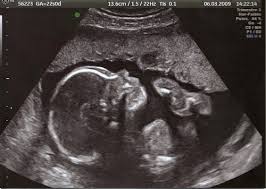

L'échograpie est une méthode d'exploration qui repose sur l'utilisation des ultrasons. Les échos renvoyés par les organes permmettant en effet de visualiser ce qui est invisible à l'oeil. Après l’application d’un gel facilitant la propagations des ondes, une sonde posée sur la peau agit comme un émetteur et recepteur de faisceaux d’ultrasons. Reliée a un amplificateur et un  écran, elle transmet des imformations qui sont alors traduites en images.

Au départ les ultrasons permettaient la détection de sous-marins pendant la 1ère guerre mondiale.L'échographie se repose sur la découverte de Pierre et Jacques Curie en 1880, puis sur les 2 Britanniques J.J. Wild et J. Reid qui en 1951 présentèrent à la communauté médicale un nouvelle appareil: l'échographe. Il était destiné à la recherche des tumeurs cérébrales mais fera carrière dans l'obstétrique en 1970.

Il existe plus de 11 types d'échographies.